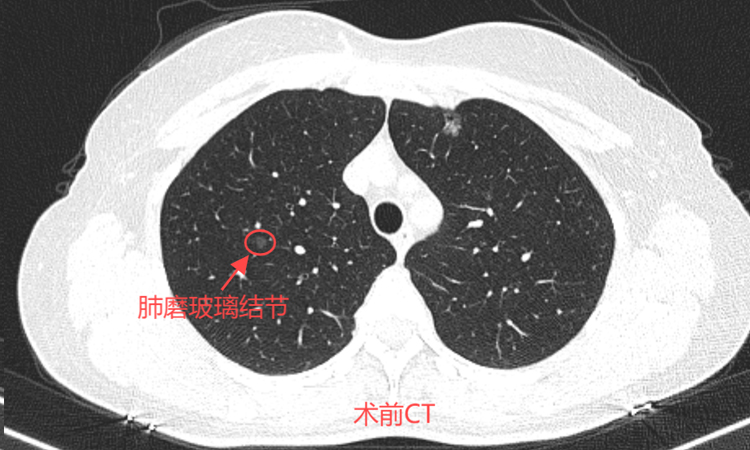

患者术前肺多发磨玻璃结节

46岁的孙女士一年前在一次偶然的体检中发现自己双肺有多发磨玻璃结节。在医生的建议下,决定先进行随访,等结节有变化了再做处理。今年复查时发现最大结节已经达0.9*0.8cm,因担心癌变可能,于近日前往北京某三甲医院就诊,看诊后专家建议行消融治疗,经过多方咨询后就诊于我院。